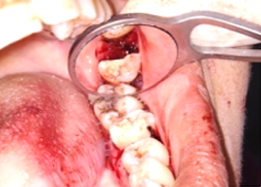

Hemisectomy

Bone Graft Placement

Placement of PRF Membrane